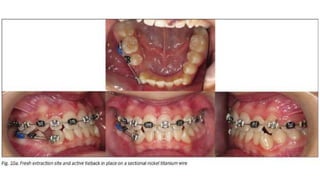

• 77.

Treatment sequencing The patient'smaxillary arch was bonded to include all teeth except unerupted canines. After three months, adequate space was created to bond the erupted canines. After six months of maxillary-only appliances, no significant mandibular growth had taken place .

• 78.

Because of this,bonding a lower sectional appliance from molar to canine on the Class III side was done . A 0.014 NiTi wire was used and an active tieback placed before dental extraction.